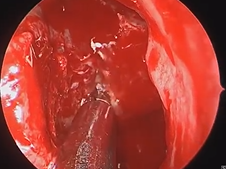

Microdirect Laryngoscopy and CO2 Laser Total Vestibulectomy for Pyolaryngocele

- Date : 01/01/2020